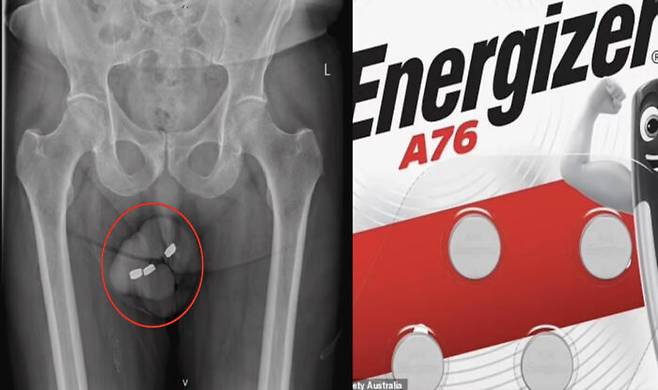

![호주의 한 남성(73)이 요도에 1.3cm 크기의 건전지 3개를 넣은 사건이 공개됐다. [사진=데일리메일 캡처]](https://img3.daumcdn.net/thumb/R658x0.q70/?fname=https://t1.daumcdn.net/news/202402/16/KorMedi/20240216170415190xyjy.jpg)

최근 영국 매체 데일리메일에 따르면 익명의 호주 남성(73)은 성적 쾌감을 위해 요도에 1.3cm 폭의 건전지 3개를 넣었다. 그는 예전에는 요도에 몇 가지를 넣었을 때 스스로 빼는데 문제가 없었는데 이번에는 빼기 어렵다고 의료진에게 전했다. 소변을 보기 어렵고 음경 통증 등의 증상이 나타나자 그는 24시간 만에 병원을 찾았다.

검사결과 건전지는 남성의 요도 깊은 곳에 위치해 있었다. 그가 무리하게 건전지를 빼내려는 탓에 밀려 들어간 것으로 추정됐다. 의료진들은 집게, 겸자(날이 없는 기다란 가위같이 생긴 의료도구) 등으로 건전지 제거에 성공했다. 제거된 건전지는 검은 타르같은 물질로 코팅돼 있었으며, 남성의 요도 입구도 검게 물든 상태였다.